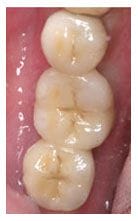

治療前

治療後